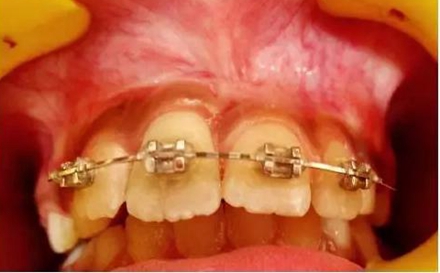

正畸牽引5周后,牙齒復(fù)位到其原始位置,與其他切牙完全對(duì)齊(圖3)。開始嘗試血運(yùn)重建。重新打開根管,使用次氯酸鈉和生理鹽水沖洗。然后插入無菌根管銼,并將其推到根尖處,以使血流進(jìn)入根管。一旦血液到達(dá)釉牙骨質(zhì)界,放置一個(gè)濕潤的無菌棉球靜置15分鐘,直到血凝塊形成,再放置約2-3mm的MAT在血凝塊上。在MAT上覆蓋一個(gè)濕棉球,隨后進(jìn)行臨時(shí)修復(fù)。以后再替換為玻璃離子水門汀墊底和復(fù)合樹脂修復(fù)。復(fù)診時(shí)間為1、3、6、9和12月。正畸復(fù)位保留12周。然而,在這么長的保留期內(nèi)還是復(fù)發(fā)了錯(cuò)位,這也強(qiáng)調(diào)了在嚴(yán)重侵入的情況下長期復(fù)位的重要性,因?yàn)槔奂暗难例X周圍出現(xiàn)大量的牙槽骨喪失(圖 4)。

牙齦: 即使病人保持良好的口腔衛(wèi)生,在正畸治療完成后,在受累的牙齒上能觀察到明顯的牙齦萎縮。系帶附著位置可能是原因之一。修整系帶可能可以解決這個(gè)問題(圖4)。在軟組織愈合后,復(fù)發(fā)的牙齒復(fù)位至正常位置(圖 5)。經(jīng)過6周病人細(xì)致的口腔衛(wèi)生維護(hù),牙齦狀況和美觀得到改善(圖6和7)。

(圖 4)